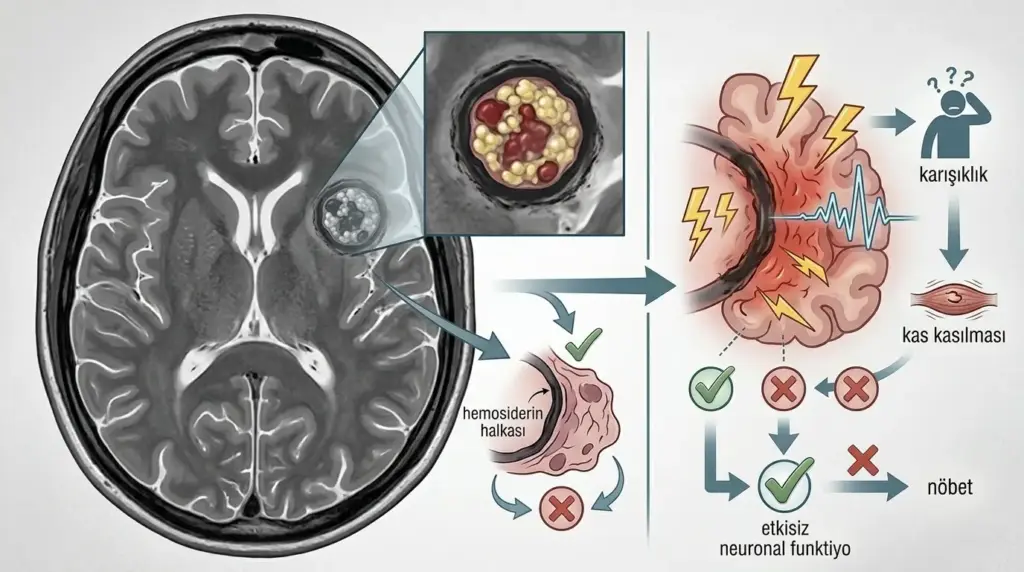

Kavernom nöbeti, beyinde ya da omurilik dokusunda yer alan serebral kavernöz malformasyonun (SKM) çevresine kronik mikrokanama yoluyla hemosiderin — yani demir içerikli kan artığı — biriktirmesi sonucu ortaya çıkan epileptik ataktır. Bu birikinti çevre beyin dokusunu sürekli tahriş eder; anormal elektrik deşarjları oluşur ve nöbet başlar.

Kavernom nöbeti, basit bir uzuvda uyuşma hissinden bilinç kaybının eşlik ettiği tonik-klonik kasılmalara kadar geniş bir yelpazede görünüm sergileyebilir. Kavernomla ilişkili epilepsinin (KİE) görülme sıklığı, supratentoryal yerleşimli lezyonlarda yüzde 23–50 arasında bildirilmektedir.

● Tekrarlayan mikrokanamalar: Her yeni kanama, hemosiderin halkasını genişletir ve çevredeki sinir dokusunu ek olarak tahriş eder.

● Birden fazla lezyon varlığı: Çok sayıda kavernomun bir arada bulunması, tek lezyon olanlara kıyasla yeniden kanama olasılığını belirgin biçimde artırır.

Kavernom, düşük akışlı yapısıyla beyin damar hastalıkları arasında görece daha az agresif seyreden bir lezyon olsa da tekrarlayan mikrokanamalar birikimsel beyin hasarı oluşturabilir.